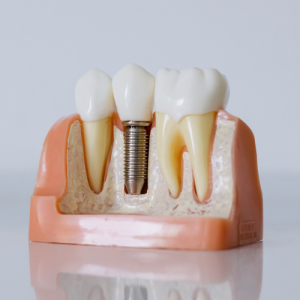

Estetik Dolgu

Röntgen ve Görüntüleme

Panoromik Film